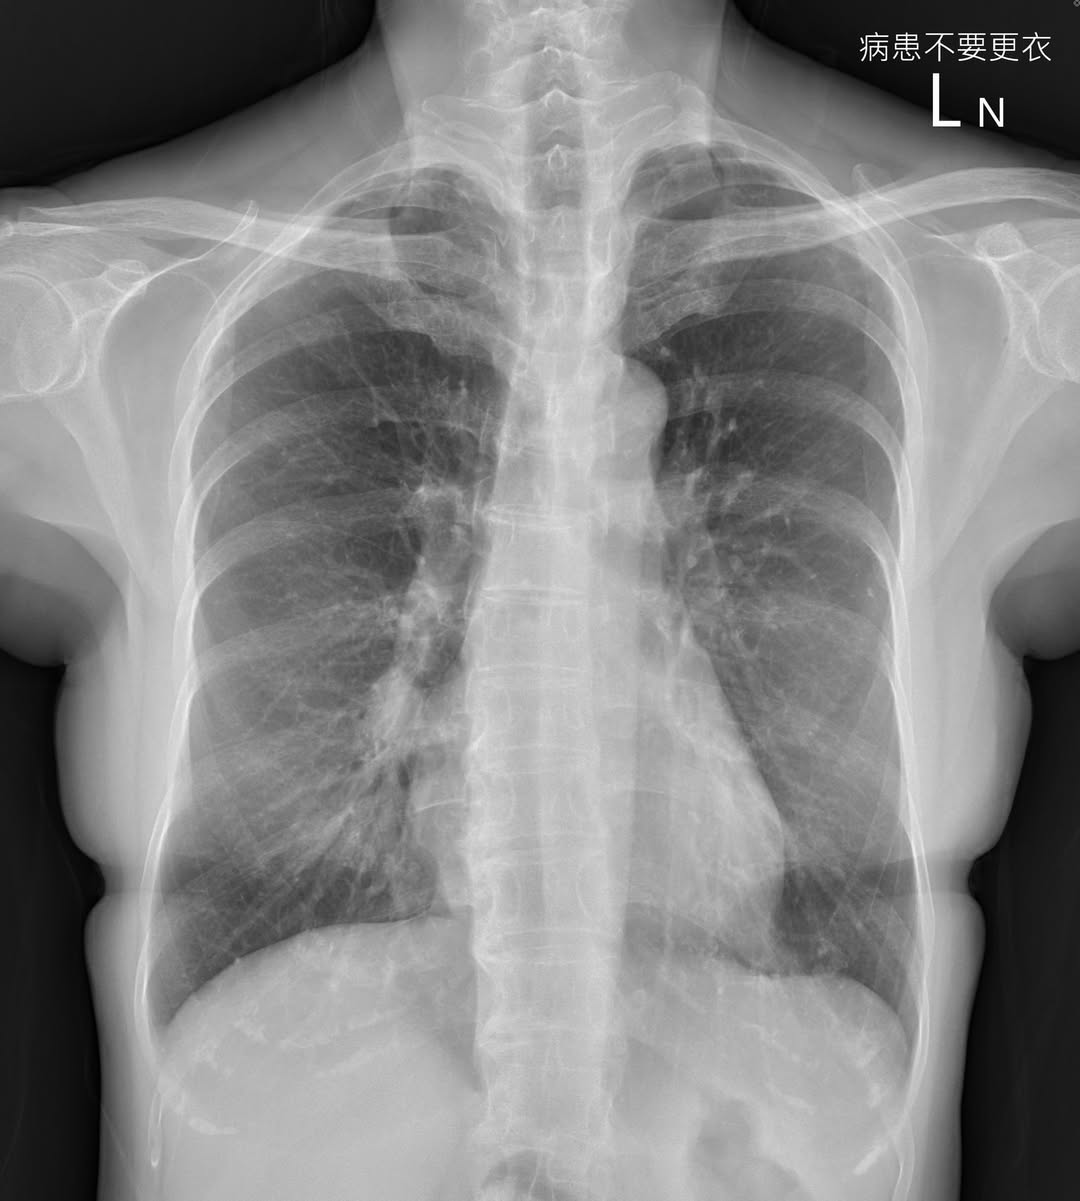

蘇一峰表示,女患者沒有抽菸習慣,卻有輕微咳嗽,半年多沒好,期間去過其他醫學中心,照X光看了沒事,判斷可能是長新冠,但治療後,咳嗽仍沒有好轉,於是到自己的門診求助。

蘇一峰迴憶,怎料X光一照,覺得大有問題,於是幫女患者安排後續的電腦斷層CT檢查,原來她肺部有3公分的腫瘤,確診為肺癌,大概第二期或三期,「當胸腔科醫師,門診X光片壓力很大啊!」